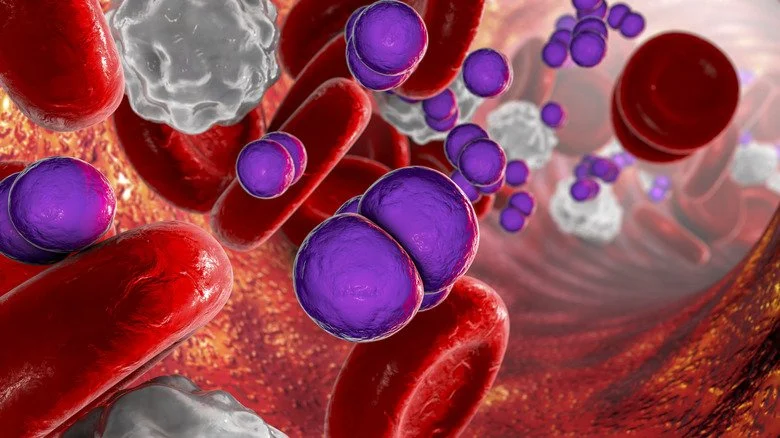

Le sepsis se produit lorsqu’un patient souffre d’une infection, généralement d’origine bactérienne, et que la réponse immunitaire est si intense qu’elle commence à endommager les organes. Cette condition, distincte de la septicémie, qui est une infection bactérienne dans le sang, peut néanmoins en résulter. Considéré comme une urgence médicale, le sepsis est considéré par l’Organisation mondiale de la santé comme l’une des principales causes de décès dans le monde, ayant causé 11 millions de décès enregistrés en 2020 parmi près de 49 millions de cas. Il est important de noter qu’il est difficile de collecter des statistiques fiables sur l’ensemble de la population mondiale, rendant très probable que ces chiffres soient sous-estimés.

Les symptômes du sepsis incluent la fièvre, des douleurs, une respiration rapide et un rythme cardiaque accéléré, pouvant évoluer vers un choc, une défaillance organique, et finalement la mort si la situation n’est pas rapidement prise en charge. Les mesures visant à prévenir le sepsis sont principalement axées sur l’hygiène, la sanitation et le contrôle des infections, toutes des pratiques difficiles à maintenir en zone de guerre.

En conséquence, le sepsis demeure une condition à forte mortalité parmi les membres des forces armées américaines, malgré les avancées médicales en matière de traitement. Une étude de l’Institut national de la santé (NIH) sur les décès parmi les soldats hospitalisés dans 19 centres de traitement durant la guerre du Vietnam a démontré que le sepsis représentait le troisième facteur de mortalité parmi les patients chirurgicaux, juste derrière les traumatismes crâniens et les pertes de sang ; et qu’il était le principal responsable des décès parmi ceux qui décédaient après les 24 premières heures passées à l’hôpital.